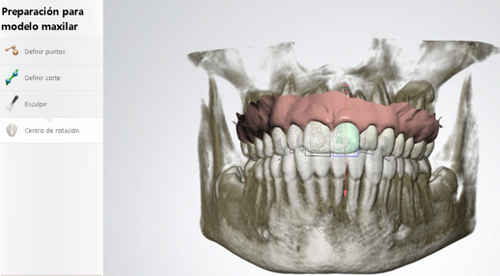

La información a la que nos estamos refiriendo la vamos a explicar punto por punto a continuación. En primer lugar, hablaremos de nuestra última incorporación en el diagnóstico que es el Escáner 3D. Es cuestión de sólo 10 minutos el poder reproducir, diente a diente, la boca de un paciente, en una pantalla a tiempo real, a todo color y con una gran calidad de la imagen. Podemos apreciar si el paciente tiene alguna pieza dental rayada, alguna parte descascarillada. Con esta prueba obtenemos el volumen y el estado de todas las piezas dentales de la arcada superior e inferior y también de cómo muerde el paciente, información clave para saber si sus dientes encajan bien o no.

Los casos quirúrgicos son aquellos en que los huesos no están coordinados. Pueden ser por inclinaciones anómalas de los maxilares como la mordida abierta o porque lo maxilares son de distintos tamaños, demasiado grande o pequeña. El cirujano tiene que colocar el hueso en la posición correcta y el ortodoncista debe colocar los dientes en posición correcta dentro del hueso para la coordinación óptima de los huesos. Para ello, a lo largo del tratamiento, se deben tomar medidas de la boca cada 2 ó 3 meses. Estas medidas se hacen con la pasta de alginato, que para algunos pacientes son una auténtica incomodidad porque les da mucha angustia. Este sufrimiento se ha acabado con el Escaner 3D. Con esta nueva tecnología podemos ir analizando cómo evoluciona la boca del paciente, que en los casos quirúrgicos se va desencajando poco a poco, con todos los datos, de las tomas iniciales, intermedias y finales, para comprobar que estás avanzando en el objetivo a alcanzar.

También con el Set Up podemos analizar qué movimientos se van a producir en los dientes del paciente hasta conseguir un engranaje perfecto para su boca. Permite ver los movimientos ortodóncicos de forma virtual, así cogemos los dientes los colocamos les damos la información del movimiento que queremos y podemos ver si van a caber o no dentro del hueso, de si van a permitir una función correcta. Con esto respondemos a preguntas fundamentales como: ¿Necesidades de espacio: expansión? ¿Tipo de anclaje: dental u óseo? ¿Necesidades de stripping(limado de dientes) o extracciones? y la pregunta más importante qué tipo de aparato de ortodoncia va a ser el mas adecuado para ese proceso.